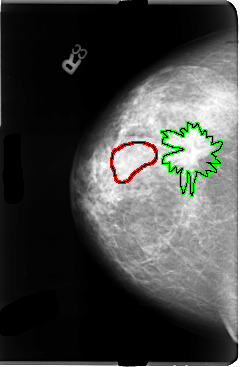

B_3036_1.RIGHT_MLO

FILE: B_3036_1.RIGHT_MLO.OVERLAY

TOTAL_ABNORMALITIES 2

ABNORMALITY 1

LESION_TYPE MASS SHAPE LOBULATED MARGINS CIRCUMSCRIBED-OBSCURED

ASSESSMENT 3

SUBTLETY 3

PATHOLOGY UNPROVEN

TOTAL_OUTLINES 1

BOUNDARY

ABNORMALITY 2

LESION_TYPE MASS SHAPE ARCHITECTURAL_DISTORTION MARGINS ILL_DEFINED-SPICULATED

ASSESSMENT 4

SUBTLETY 4

PATHOLOGY MALIGNANT